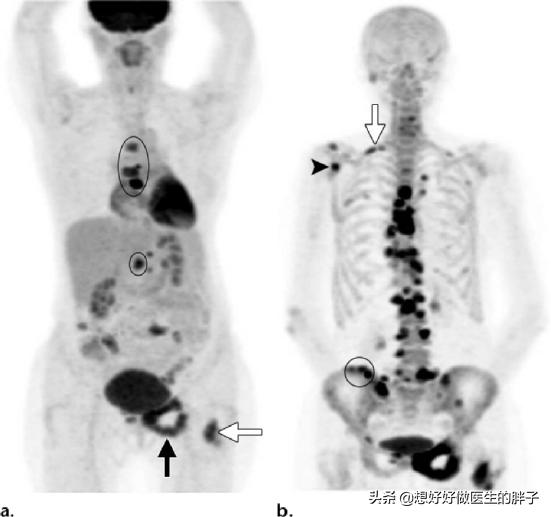

がんの既往歴がなく、家計に余裕がある患者には、全身にがんの疑わしい病変がないかスクリーニングするためにPET-CT検査を行うことが推奨され、これにより腫瘍病変の有無、進行度、どのような転移病巣があるかなどを適切に判断することができる。

がんの既往があり、その時点で悪性度が高いと判断されれば、全身骨シンチで骨転移の有無を調べることができる。同時に、転移部位の骨破壊の程度を磁気共鳴検査で明らかにすることができる。

疼痛は骨転移のほとんど(80%以上)の初期症状であり、一部の転移は非常に若年で発現する。骨痛、骨折、アルカリホスファターゼ上昇、高カルシウム血症などの骨転移が疑われる乳癌に対しては、骨放射性核種スキャン(ECT)を行うことができる。PET/CTはECTと同程度の感度で特異度が高く、乳がん骨転移の治療後の経過観察に使えるという研究もあります。診断が困難な場合は、必要に応じて骨の一部を切除して病理検査を行うこともある。

溶骨性、造骨性、混合性骨破壊のX線所見も、転移性骨癌の可能性を考慮すべきである。転移性骨腫瘍を検出するには、適時の骨スキャンが感度の高い方法である。